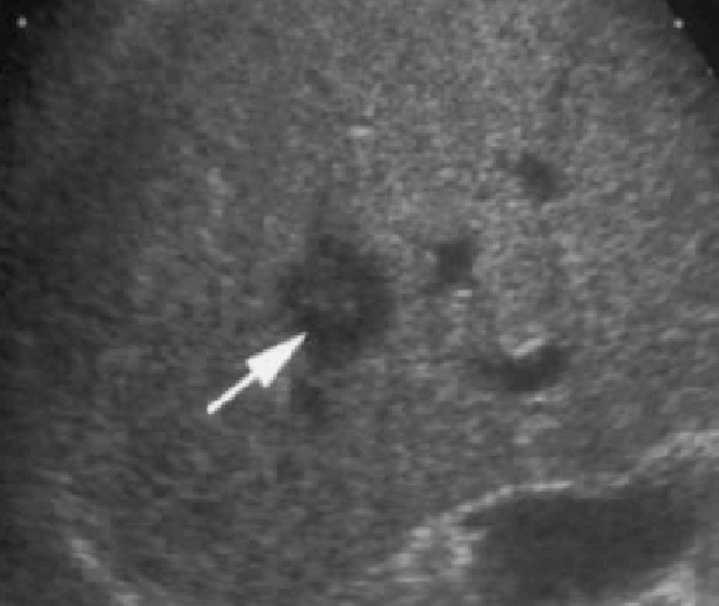

① <2cm small hcc sono finding

- well define

- round shape

- hypoechoic / hyperechoic, bright loop sing pattern (지방화, 탈분화 동반 경우 드물게 보임)

- irregular / indistinct margin

- halo (-)